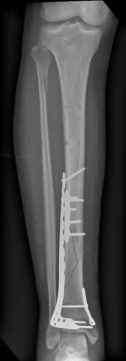

With the articular surface reconstituted, the surgeon's focus shifts to bridging the complex metaphyseal-diaphyseal dissociation. A pre-contoured anatomical locking plate is slid submuscularly or subcutaneously along the diaphysis using a MIPPO technique. The plate is positioned on the anterolateral or medial surface, depending on the preoperative plan and soft tissue constraints.

The distal portion of the plate is secured to the reconstructed articular block. It is imperative that the distal locking screws are placed parallel to the joint space, forming a rigid subchondral raft that supports the articular cartilage. Fluoroscopy is utilized extensively to ensure no screws have penetrated the joint. Once the distal block is secured to the plate, the diaphyseal segment is aligned. Length, alignment, and rotation are restored using manual traction or the femoral distractor. The proximal portion of the plate is then secured to the diaphysis using a combination of non-locking screws (to pull the bone to the plate) and locking screws (to create a fixed-angle construct). The working length of the plate is maximized by leaving several screw holes empty over the zone of comminution, promoting secondary bone healing.